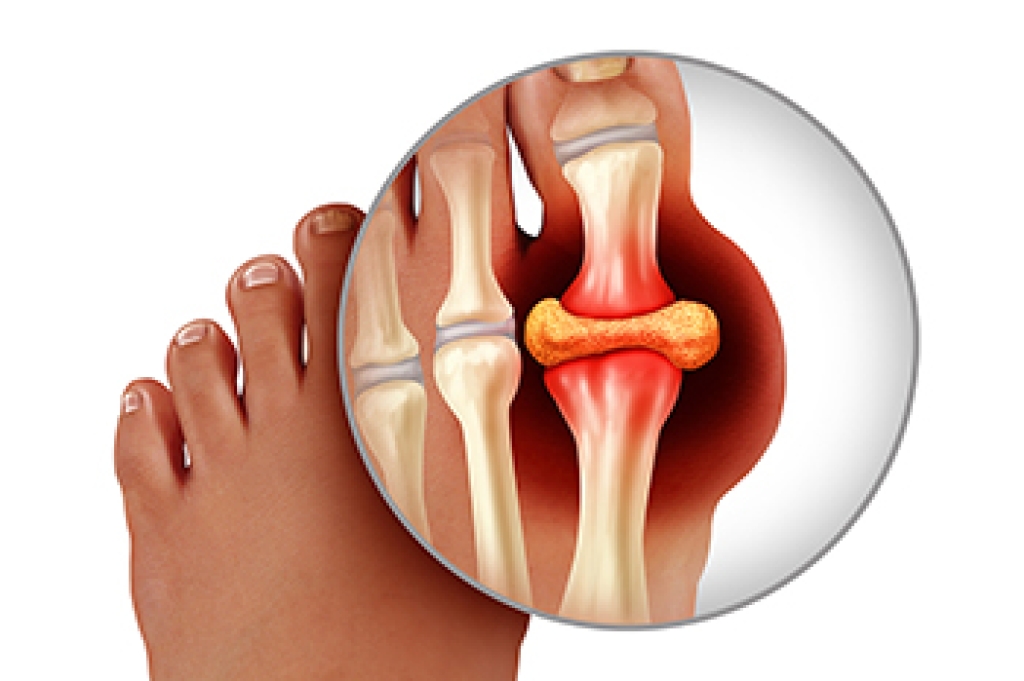

A common form of inflammatory arthritis is known as gout. It can be extremely uncomfortable and can cause severe pain. It frequently affects the joints in the big toe, and may make walking difficult. Gout develops as a result of a buildup of uric acid, which may come from specific foods, including red meat and shellfish, as well as drinking alcoholic beverages. In addition to pain in the big toe, common symptoms can consist of swelling, redness, and lumps that are painless under the skin. Prevention methods include losing excess weight, avoiding foods that can trigger gout attacks, and eating foods high in vitamin C. Additionally, implementing a gentle exercise routine may help to manage gout. If you have this type of pain in your big toe, please speak with a podiatrist who can discuss prevention techniques and offer treatment solutions.

Gout is a form of arthritis that is characterized by sudden, severe attacks of pain, redness, and tenderness in the joints. The condition usually affects the joint at the base of the big toe. A gout attack can occur at any random time, such as the middle of the night while you are asleep.

- Inflammation and Redness -Affected joints may become swollen, tender, warm and red